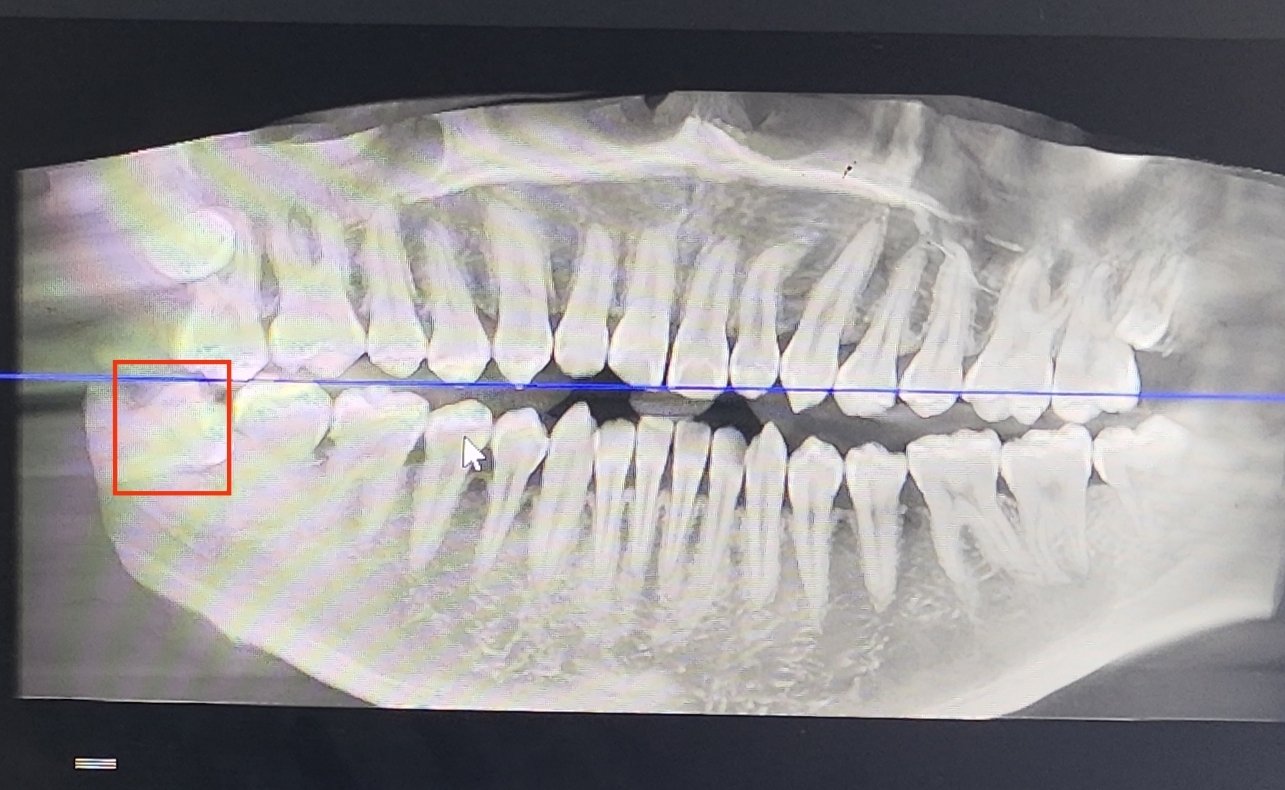

四个智齿,没一个老老实实的

(右下的智齿已经不得不拔了,因为这颗是横向180°长出来的,已经顶到隔壁牙齿了)